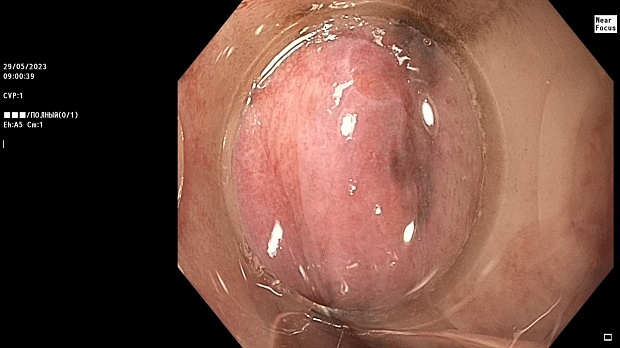

Иллюстрация №2: Эндофото. Сидероз нижней трети пищевода, осмотр в белом свете в близкофокусном режиме

Согласно полученным данным - в среднегрудном и нижнегрудном отделах пищевода определялась проксимальная граница плоских неправильной формы поверхностных рубцов суммарной протяженностью до 8,0 см. На этом фоне в зонах поверхностных рубцов по задней полуокружности визуализировались участки гиперпигментации в темный цвет (Рис. 1). При исследовании в режиме Dual Focus было отмечено наличие мелких (до 0,001 см) черно-коричневых включений, расположенных субэпителиально - в строме слизистой оболочки, сливания их в единый конгломерат не определялось (Рис. 2). При эндосонографии с применением минидатчика с частотой сканирования 20МГц выявлено, что все слои стенки четко дифференцируются, не утолщены, в слизистой оболочки визуализированы мелких гиперэхогенные включения с эхотенями (Рис. 3).

В пищеводе в шейном его отделе на уровне 16 см от резцов циркулярно визуализированы единичные синюшные флебоэктазии размерами до 0.5 см. Дистальнее пищевод визуально не изменен до уровня 28 см от резцов, где определяется проксимальная граница плоских неправильной формы поверхностных рубцов, распространяющихся до уровня 36 см от резцов. На этом фоне в зонах поверхностных рубцов по задней полуокружности визуализированы участки гиперпигментации в черно-коричнеый цвет. При осмотре в режиме Near Focus с увеличением - между зон пигментации определяются расширенные капилляры типа II по Inoue-классификации. При биопсии отмечена десквамация плоского эпителия, визуализированы мелкие черно-коричневые включения в строме слизистой оболочки, размеры их до 0,001 см, сливания их в единый конгломерат не отмечается. При эндосонографии с датчиком 20Мгц в исследуемой зоне в слизистой оболочке определяются гиперэхогенные включения, в то время как в подслизистом слое - зоны со сниженной эхогенностью. При биопсии отмечается уплотнение ткани, однако истинной фрагментации не определяется. Уровень Z-линии совпадает с уровнем анатомического кардиоэзофагеального перехода. Розетка кардии эластичная, смыкается не полностью, расположена на уровне пищеводного отверстия диафрагмы.